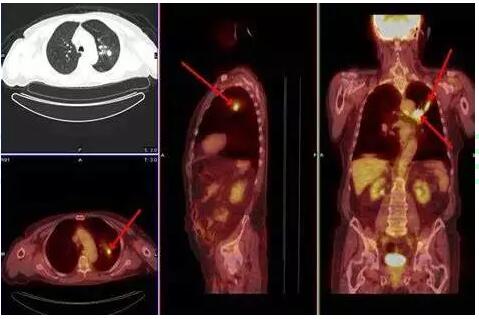

No.6 正电子发射体层摄影(PET)

PET-CT是将影像学和放射性核素融为一体的新型检查方法,可以发现普通CT不能发现的微小病灶,但价格昂贵,一般是自费,不能医保报销的,如果有条件可以考虑。需要注意的是,由于脑组织是高代器官,PET-CT对脑部转移显示不清,判断有无脑转移还是考虑行脑CT或脑部磁共振检查。